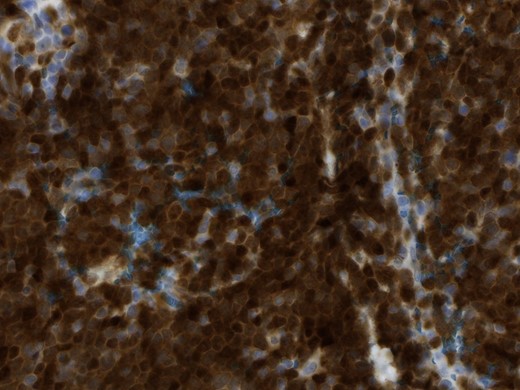

In the pathological assessment the appendix measured 10 and 4.5 cm in diameter. Histopathology revealed an infiltrating non-Hodgkin lymphoma, blastoid B-cell-type, a mantle cell lymphoma. The immunohistochemical pattern was positive for CD20, CD5, Cyclin D1, bcl-6 (that fits for blastoid type), negative for CD3, CD23 and CD10. MIB-1 was up to 75% (Figs 4 and 5).

Magnification 40×, the immunohistochemical staining shows strong diffuse nuclear expression of Cyclin D1 (>95% of all mantle cell lymphoma including CD5-negative cases).